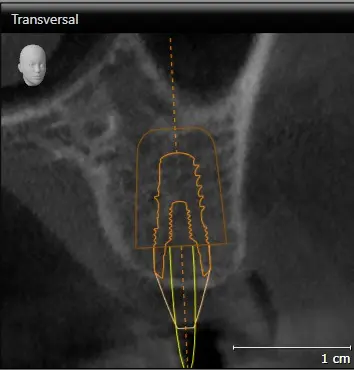

TOMOGRAFÍA PARA ENDODONCIA

Evaluación necesaria en campo reducido para visualizar los conductos radiculares o probables fracturas.